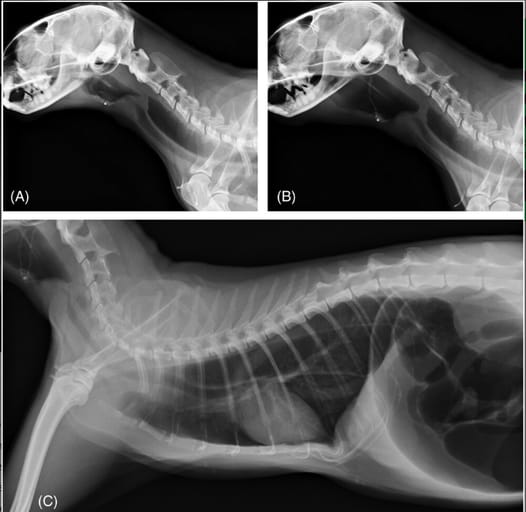

Right lateral cervical expiratory (A) and inspiratory (B) radiographs, and right lateral thoracic radiograph (C) of a cat with inflammatory laryngeal disease (Cat 3). In the inspiratory phase, a laryngeal mass is severely displaced caudally at the level of C3, and the oropharynx is markedly gas-distended. The hyoid apparatus appears L-shaped and is severely displaced caudally. The soft palate remains in a normal position. The esophagus is generally and severely gas-distended with a ventral deviation of the thoracic trachea, and the included gastrointestinal tract is also severely distended with gas.